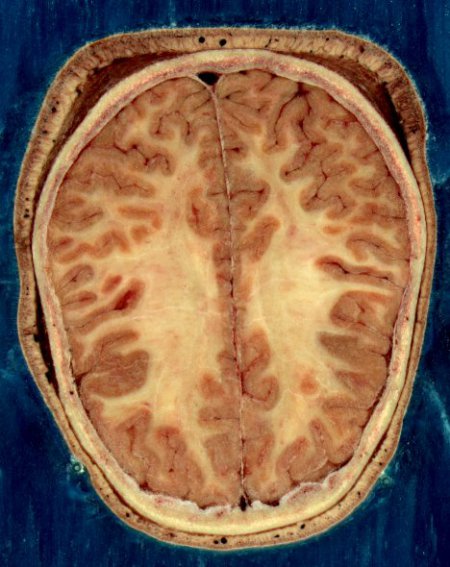

The device is made of layers of silicon and molybdenum that can measure physiological characteristics and dissolve at a known rate, as determined by its thickness. For example, the team used the device to record brain waves in rats under anesthesia, as well as voltage fluctuations between neurons (EEGs), and induced epileptic spikes in intact live tissue. A separate experiment demonstrated a complex, multiplexed array made from these materials that could map rat-whisker sensing capabilities at high resolution.

These electrophysiological signals were recorded from devices placed at the surface of the brain cortex (the outer layer of tissue) and the inner space between the scalp and skull. Chronic measurements were made over a 30-day period, while acute experiments demonstrated device operations over three to four hours.